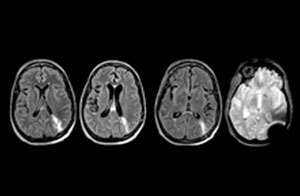

Clinical cases